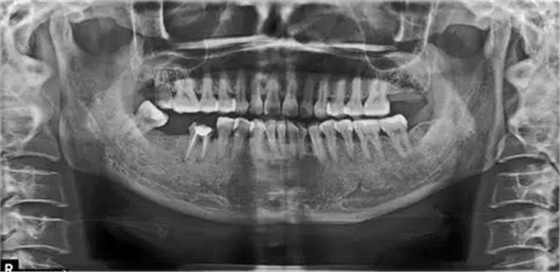

病例2:T女士,42歲。左上后牙缺失3年。就診要求恢復咀嚼功能。

X片上可見T女士左上后牙缺失。根據(jù)患者口內(nèi)和全身狀況。制定計劃為:右上后牙種植修復。